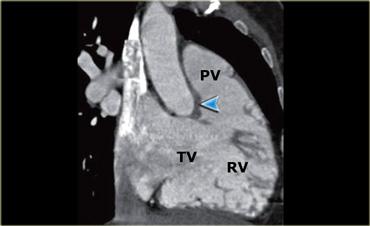

Hình tái tạo cho thấy van ba lá (TV) và van động mạch phổi (PV) cùng với buồng thất phải (RV). Mũi tên xanh chỉ mào trên thất (crista supraventricularis)

Van động mạch phổi

Tiếp theo, máu chảy về phía van động mạch phổi – trước tiên đi vào phễu cơ trơn của thất phải.

Van động mạch phổi có ba lá van, và được tách biệt với van ba lá bởi một khối cơ dày gọi là mào trên thất (mũi tên xanh trong hình bên trái).

Điều này khác với đường ra thất trái, nơi van hai lá và van động mạch chủ nằm cạnh nhau.

Bên trái là bảng tóm tắt các đặc điểm đặc trưng của thất phải, hữu ích trong việc phân biệt thất trái với thất phải trong các trường hợp tim bẩm sinh phức tạp.